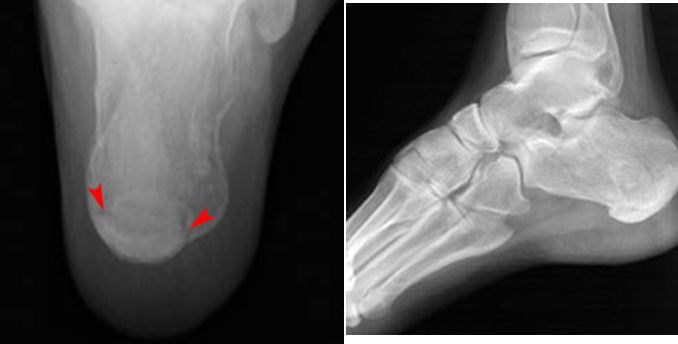

跟骨骨折

疼痛科怎么理疗疼痛科医生、康复理疗科医生、针刀针灸医生应掌握的常见骨科疾病X光片_https://www.jmylbn.com_新闻资讯_第44张

Jones Fracture

• 第五跖骨基底部骨折

• 易漏诊

• 不制动易致骨不连